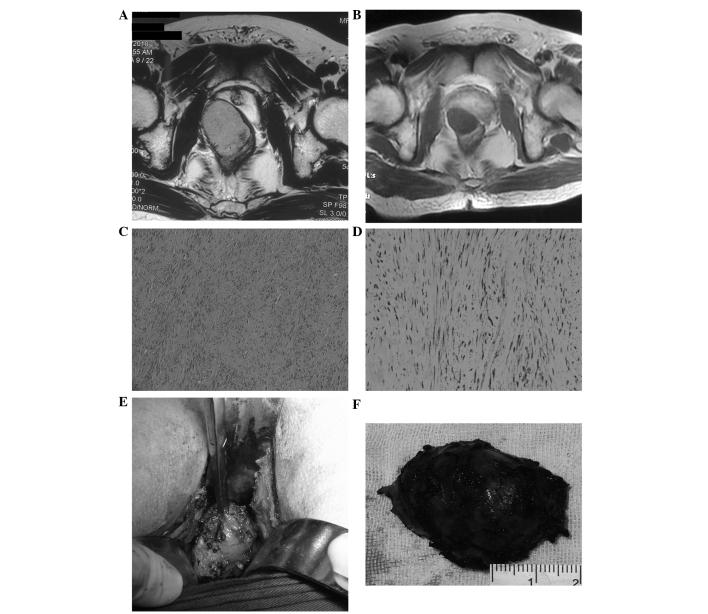

Gastrointestinal stromal tumors (GISTs) are rare in the rectum. Radical surgery, such as an abdominoperineal resection, is necessary for large rectal GISTs, which can result in the loss of function of involved organs. Imatinib mesylate can be used as perioperative therapy and may reduce tumor size, and it is now approved for use in the adjuvant therapy of locally resected anorectal GISTs. The present study describes two cases of large rectal GISTs, for which abdominoperineal resections were initially planned. The two patients received pre-operative imatinib mesylate treatment, and the therapeutic response was assessed by magnetic resonance imaging. Finally, transsacral local resection was successfully performed for these two GISTs. A macroscopically complete resection was achieved, and microscopically, the resection margin was negative. One patient experienced the complication of rectal leakage, which was successfully managed by drainage. No recurrence occurred in the two patients after more than two years. Pre-operative imatinib mesylate therapy with subsequent transsacral local resection for selected rectal GISTs is a feasible treatment modality and can prevent extended surgery.

胃肠道间质瘤(GISTs)在直肠中较为罕见。对于较大的直肠GISTs,根治性手术如腹会阴联合切除术是必要的,但这可能导致受累器官功能丧失。甲磺酸伊马替尼可作为围手术期治疗用药,可能会缩小肿瘤大小,目前已被批准用于局部切除的肛管直肠GISTs的辅助治疗。本研究描述了两例较大的直肠GISTs病例,最初计划行腹会阴联合切除术。这两名患者接受了术前甲磺酸伊马替尼治疗,并通过磁共振成像评估治疗反应。最后,成功地对这两个GISTs进行了经骶骨局部切除术。实现了宏观上的完整切除,显微镜下切除边缘为阴性。一名患者出现直肠渗漏并发症,通过引流成功处理。两名患者两年多来均未复发。术前甲磺酸伊马替尼治疗随后对选定的直肠GISTs进行经骶骨局部切除术是一种可行的治疗方式,可避免扩大手术。